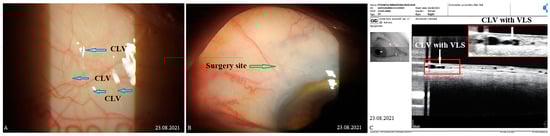

OCT images taken prior to and following the surgery were acquired by using the commercially available SOCT Copernicus Revo 80, using the technique described earlier [18], and were evaluated as described by Kawana K. et al. [21]. In Figure 1, an example of the OCT evaluation of the surgery and adjunct sites is presented.

Figure 1. OCT evaluation: (A) OCT scan of the surgery site, showing the collagen implant in the intrascleral reservoir, covered by a superficial scleral flap (SSF) and conjunctiva (CO). No filtration bleb cavity can be observed over the implant or in the nearby area. A conjunctival lymphatic vessel (CLV) can be observed running horizontally over the surgical site. (B) OCT scan of conjunctiva adjacent to the surgical site showing a CLV with valve-like structures (VLSs) in its lumen (white and black arrows with black and white borders). CO = conjunctiva; CLV = conjunctival lymphatic vessel; SSF = superficial scleral flap; VLS = valve-like structure.